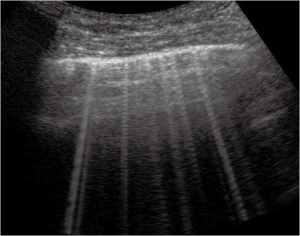

Thickened (but anatomically intact) secondary interlobular septa may act as acoustic traps where specific frequencies give rise to separated, uniform, bright and long B-lines, without spared areas (septal pattern, see Figures 1 and 2), especially in early CPE (Figure 1) (17). In ARDS subpleural random peri and intralobular distortion may explain the appearance of acoustically permissive irregular channels, different arrangements of B-lines, pleural irregularities, consolidations, and inhomogeneous isolated air spaces. Inhomogeneous edema, alveolar collapses and pulmonary fibrosis contribute to the development of the pleural irregularities that are seen in ultrasound and to the reduction of the pulmonary compliance and pleural sliding in ARDS (Figure 3) (9).

Focal findings, consolidations, spared areas, pleural irregularities and impaired pleural sliding are typical signs of primitive lung involvement. SIS with bright, long, separated, modulated B-lines arising from a normal pleural line is strongly predictive of early CPE. Figure 2 illustrates an algorithmic approach used in our clinical practice.